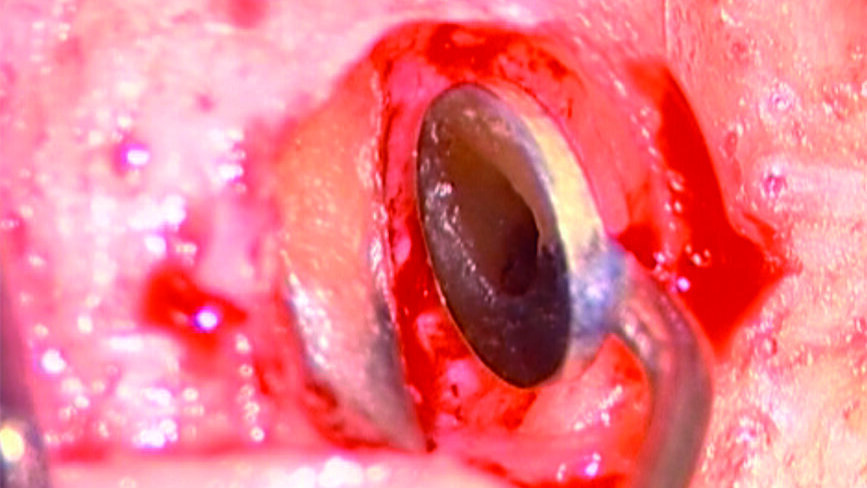

Le perforazioni del terzo medio avvengono nella maggior parte dei casi durante la preparazione della cavità d’accesso o, più spesso, durante le fasi di detersione e sagomatura o infine durante la preparazione dello spazio per un perno con l’utilizzo di frese tipo Largo, Peeso, Gates Glidden o simili (Figg. 2a-2f).

Perforazioni del terzo coronale e delle biforcazioni

Tali perforazioni sono piuttosto frequenti a livello degli incisivi superiori, dove l’errore che più spesso viene commesso è rappresentato dall’utilizzo della fresa con eccessiva angolazione vestibolare. Perforazioni del terzo coronale possono anche accadere sul pavimento dei molari quando gli orifizi canalari vengono cercati in posti sbagliati. Tipiche sono le perforazioni nei molari superiori o inferiori, che avvengono per lo sfondamento del pavimento della camera pulpare (Figg. 3a-3i). Come conseguenza del trauma meccanico, si ha una rapida distruzione del legamento parodontale. L’osso alveolare immediatamente adiacente alla perforazione si riassorbe con conseguente perdita verticale di osso. Il processo infiammatorio quindi si estende coronalmente lungo le fibre del legamento parodontale, con distruzione del legamento, dell’osso alveolare e delle fibre gengivali sopracrestali. Come conseguenza di ciò, si ha la migrazione apicale dell’attacco epiteliale e le formazione di un grave difetto parodontale9.